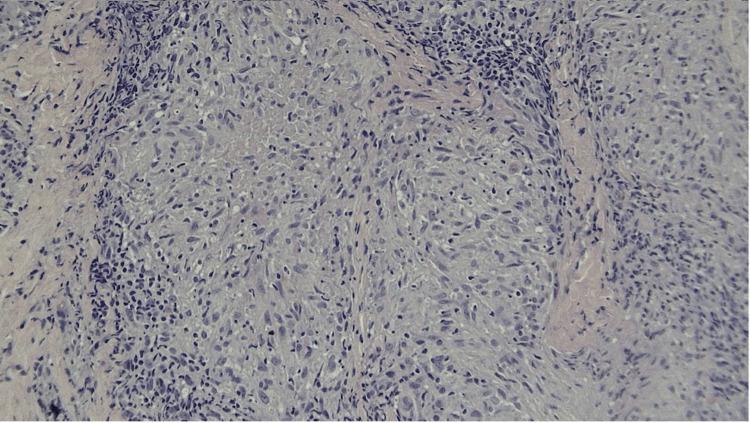

Permanent cosmetic procedures including tattooing are determined as risk factors that prompt the development of cutaneous granulomatous conditions. Scar sarcoidosis is an uncommon manifestation of a systemic granulomatous disease with a few cases reported in the literature worldwide. Although the incidence rates of sarcoid lesions at sites of pigment deposition are low, granuloma formation can provoke a severe systemic inflammatory response. We report a 48-year-old Hispanic female with a new onset of scar sarcoidosis that progressed to a systemic condition. Erythematous maculopapular eruptions arose on her left eyebrow area at the sites of scars from cosmetic tattooing, prior to exacerbation of the small airway disease. Histopathologic examination revealed typical findings of cutaneous sarcoidosis, including non-caseating epithelioid granulomas. This case highlights the importance of early detection of cutaneous sarcoidosis in long-standing scars due to the associated risks of systemic sarcoidosis.

包括纹身在内的永久性美容手术被确定为促使皮肤肉芽肿性疾病发生的风险因素。瘢痕结节病是一种系统性肉芽肿性疾病的罕见表现,全球文献中仅有少数病例报道。尽管色素沉着部位的结节病病变发生率较低,但肉芽肿形成可引发严重的全身炎症反应。我们报告了一名48岁的西班牙裔女性,她新发瘢痕结节病并进展为全身性疾病。在小气道疾病加重之前,她左眉部因美容纹身留下的瘢痕部位出现了红斑性斑丘疹。组织病理学检查显示为皮肤结节病的典型表现,包括非干酪样上皮样肉芽肿。该病例强调了由于存在系统性结节病的相关风险,早期发现长期瘢痕中皮肤结节病的重要性。